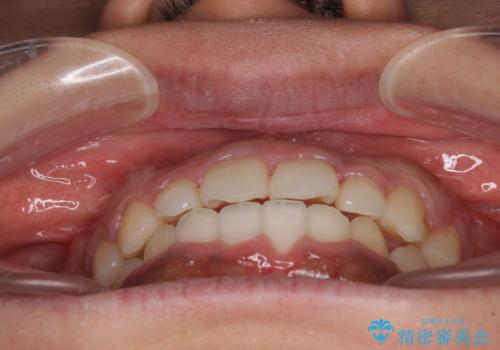

- 上下前歯の叢生を気にして来院された患者様です。

当初はインビザラインにて治療を開始しましたが、自己管理による治療が難しくなり、ワイヤー矯正へ転換して継続しました。

2年ほどインビザライン矯正を続けましたが、終了することができず、ワイヤーへ転換後は1年弱で終えることができました。